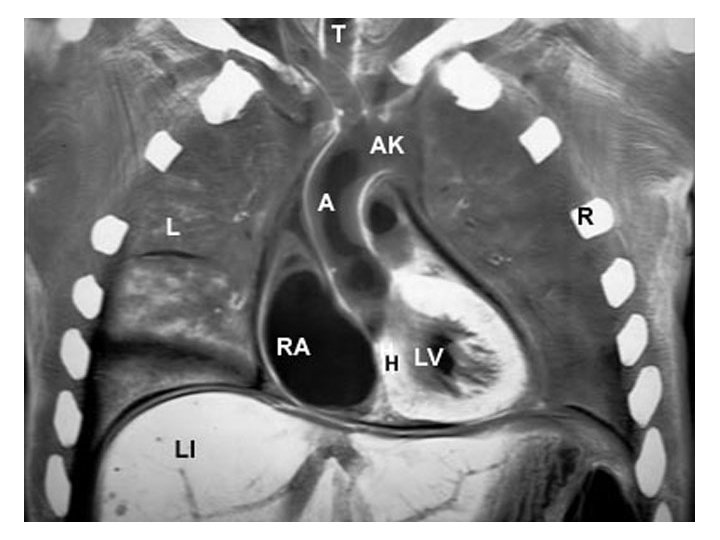

Left RV RA LV LA